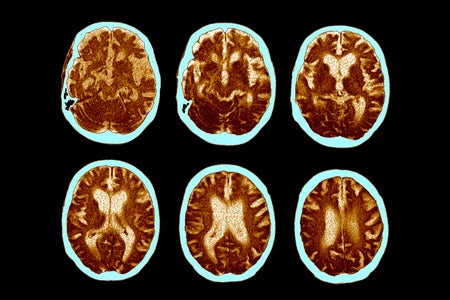

Controversial New Guidelines Would Diagnose Alzheimer’s before Symptoms Appear

According to expert recommendations, the diagnosis of Alzheimer’s can proceed by detecting the disease’s underlying biology—even before the onset of cognitive decline